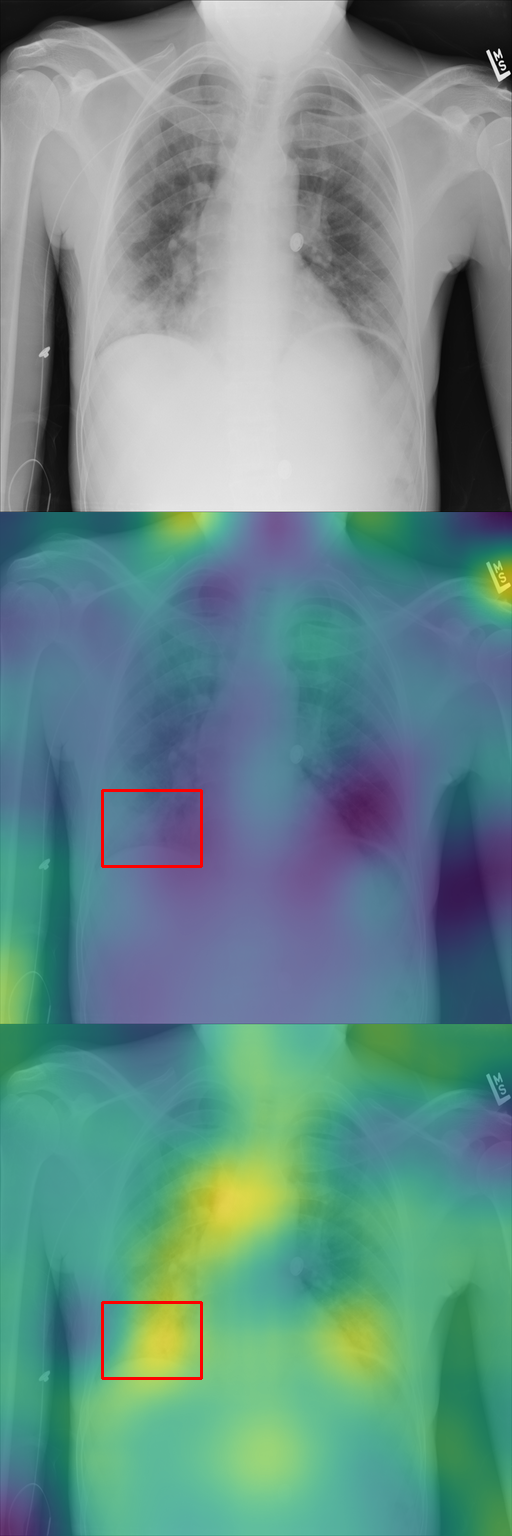

Effect of finetuning. Unsurprisingly, we found that finetuning the diffusion model on the dataset of interest was critical to the quality of our results. First, on a given image, finetuning changes the spatial distribution of typicality, prioritizing elements more correlated with the training labels (see Fig. 3(a)). Second, in Fig. 3(b), we show the most typical clusters identified before and after finetuning. The patches selected after finetuning avoid the biases in the training data of the base model and are more specific to the G ^3 dataset, identifying elements such as post-boxes. We also demonstrate this quantitatively in Section 5.2 for our application to X-ray images. Third, finetuning enables better translation between labels (see Sec. 5.1), as can be seen in Figure 3(c), allowing vegetation, roads, road tracks, and utility poles to be translated consistently across the class labels in the parallel dataset (which can be found in the supplementary material).

Our typicality score allows us to explore two different applications. First, in Section 5.1, we translate geographical elements across locations and mine typical translations. Then, in Section 5.2, we show how disease localization emerges from typicality when training to generate frontal X-rays of patients, of various diseases.

5.2 Analysis of Medical Images

In Section 4.2, we discussed how typicality helps find relevant patches for an input label. In this section, we test this idea on completely different images: X-rays of patients who may suffer from a combination of various thorax diseases. We finetune Stable Diffusion on the ChestX-ray8 dataset [46] containing 108,948 frontal-view X-ray images annotated with 14 single-word disease-name labels. Experts annotated a test set of 879 images with 7 diseases with rectangular regions of interest (ROI) for each disease. For each image, we compute typicality per latent feature, interpolate the resulting typicality to the input dimension, and blur the resulting typicality map for visualization. In Fig. 11, we show the resulting typicality maps together with the ROI annotation before and after finetuning. Finetuning clearly improves the localization. We quantify this effect by computing the area under the precision recall-curve [5] (AUC-PR) associated with the ROIs. As reported in Fig. 11, we see consistent improvement of this measure when finetuning the network (from 3.2% to 9.6%), ranging from +3.5% for Pneumonothorax (from 3% to 6%) to +14.6% for Mass (from 2% to 16.6%), which are respectively the least and most localized diseases. Similar to our other experiments, finetuning uses only image labels without localization supervision.